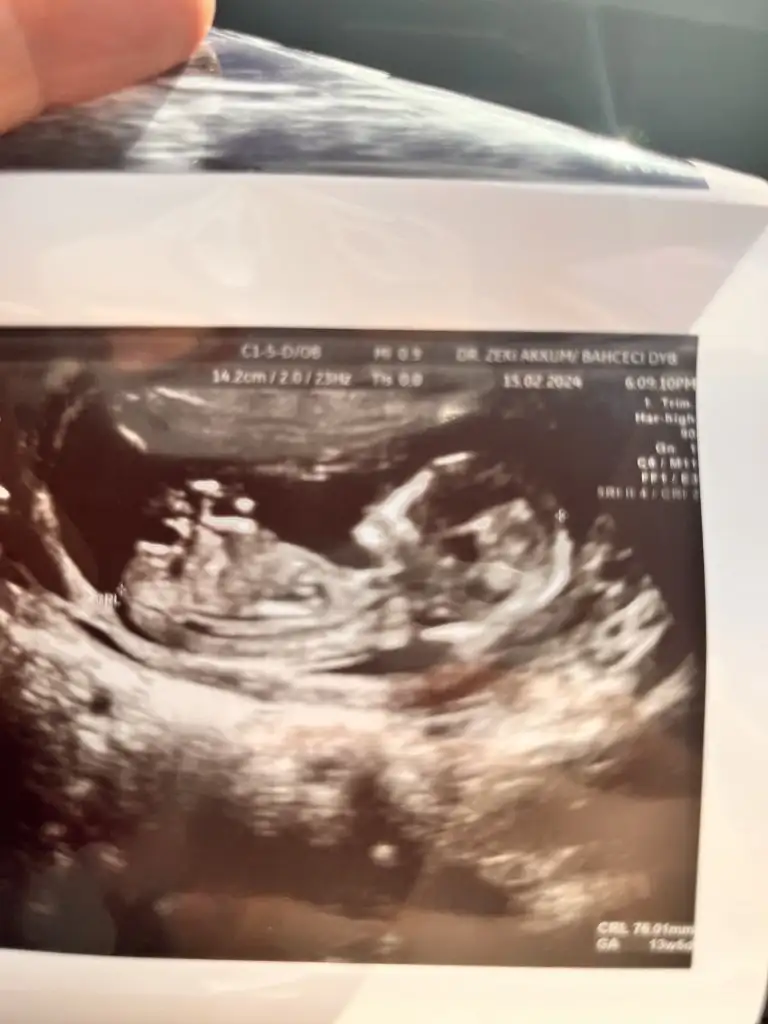

12 haftalık böyle fotomuz var bir çıkıntı var gibi ama kız da olabilir dedi doktorumuz bilemedik anlayan var mıdır 🥳

12 haftalık böyle fotomuz var bir çıkıntı var gibi ama kızlarda da olabiliyormuş doktor kesin bir şey demedi. Anlayan var mıdır acaba 🥳